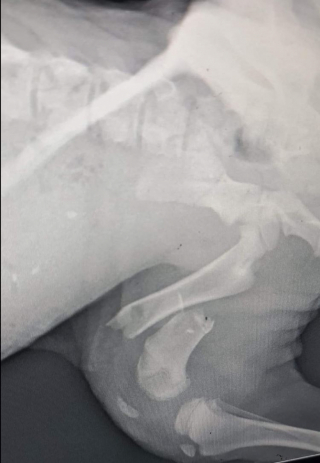

Rita était dans un état encore plus inquiétant que ses frères. En effet, elle souffrait de plusieurs fractures, au fémur et au bassin. Les vétérinaires redoutaient aussi que l’un de ses os soit atteint d’une infection bactérienne, qui mettrait alors sa vie en danger, car celle-ci risquait de se transformer en gangrène.

© Rainbow Bridge Can Wait Rescue and Adoption / Facebook

Pour la sauver, les médecins n’avaient pas d’autre choix que de l’opérer en urgence, afin d’éliminer l’infection. L’intervention était cependant très coûteuse. Ses soins s’élevaient en effet à plus de 3 000 €, sans compter le coût des soins pour remettre ses frères sur pattes. alors les bénévoles ont fait appel à leur communauté internet.